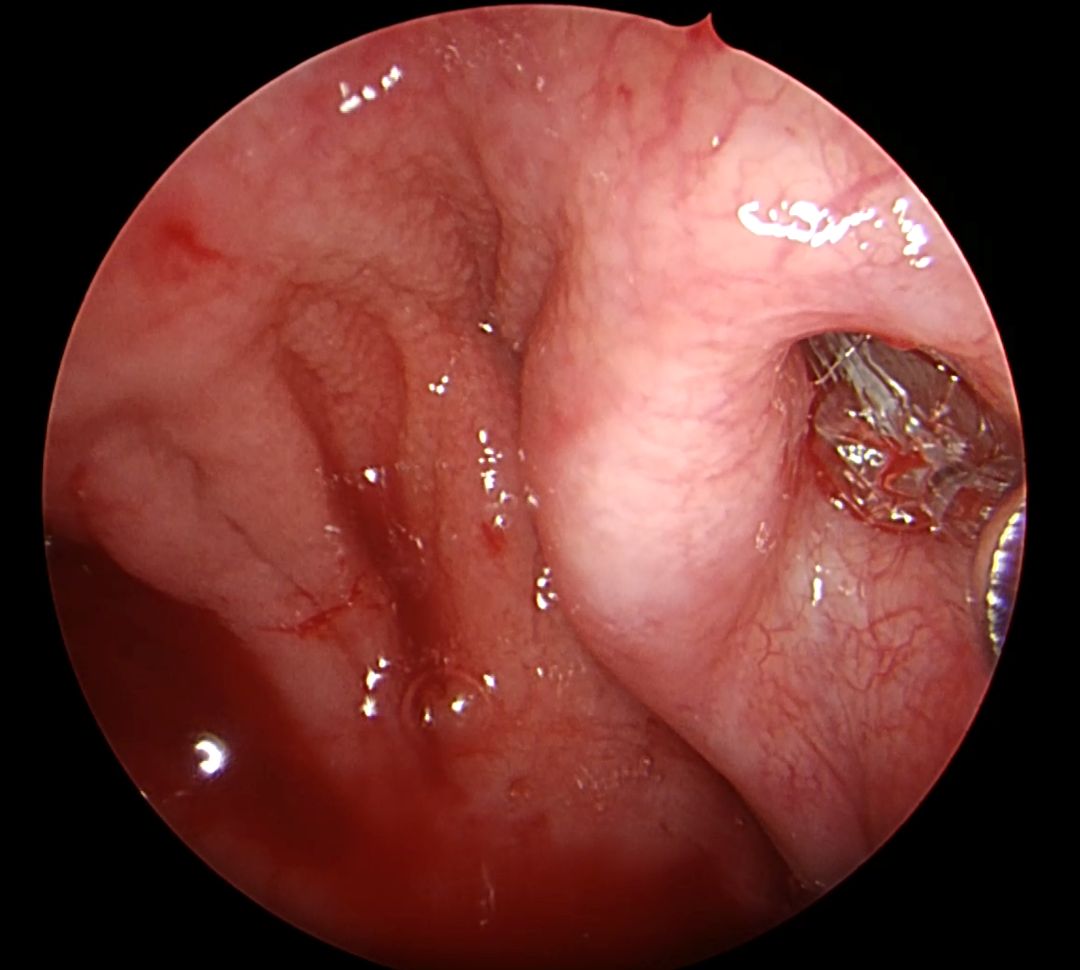

Balonikowanie trąbek słuchowych (trąbek Eustachiusza) to innowacyjna, małoinwazyjna metoda terapeutyczna stosowana u pacjentów z ich przewlekłą dysfunkcją. Schorzenie to może objawiać się uczuciem pełności w uszach, autofonią, pogorszeniem słuchu, nawracającymi infekcjami oraz trudnościami w wyrównywaniu ciśnienia – szczególnie odczuwalnymi podczas lotów samolotem czy nurkowania. Zabieg polega na wprowadzeniu przez jamę nosową cienkiego cewnika zakończonego balonikiem do ujścia gardłowego trąbki słuchowej, pod kontrolą endoskopową. Następnie balonik jest stopniowo wypełniany solą fizjologiczną, co pod działaniem ciśnienia około 10-12 atmosfer powoduje poszerzenie i przywrócenie drożności. Po krótkim czasie balon zostaje opróżniony i usunięty. Cała procedura wykonywana jest w znieczuleniu ogólnym i nie wymaga wykonywania widocznych nacięć.

Procedurę wykonała dr n. med. Marta Kwiatkowska, specjalizująca się m. in. w endoskopowej chirurgii ucha środkowego i zatok przynosowych.